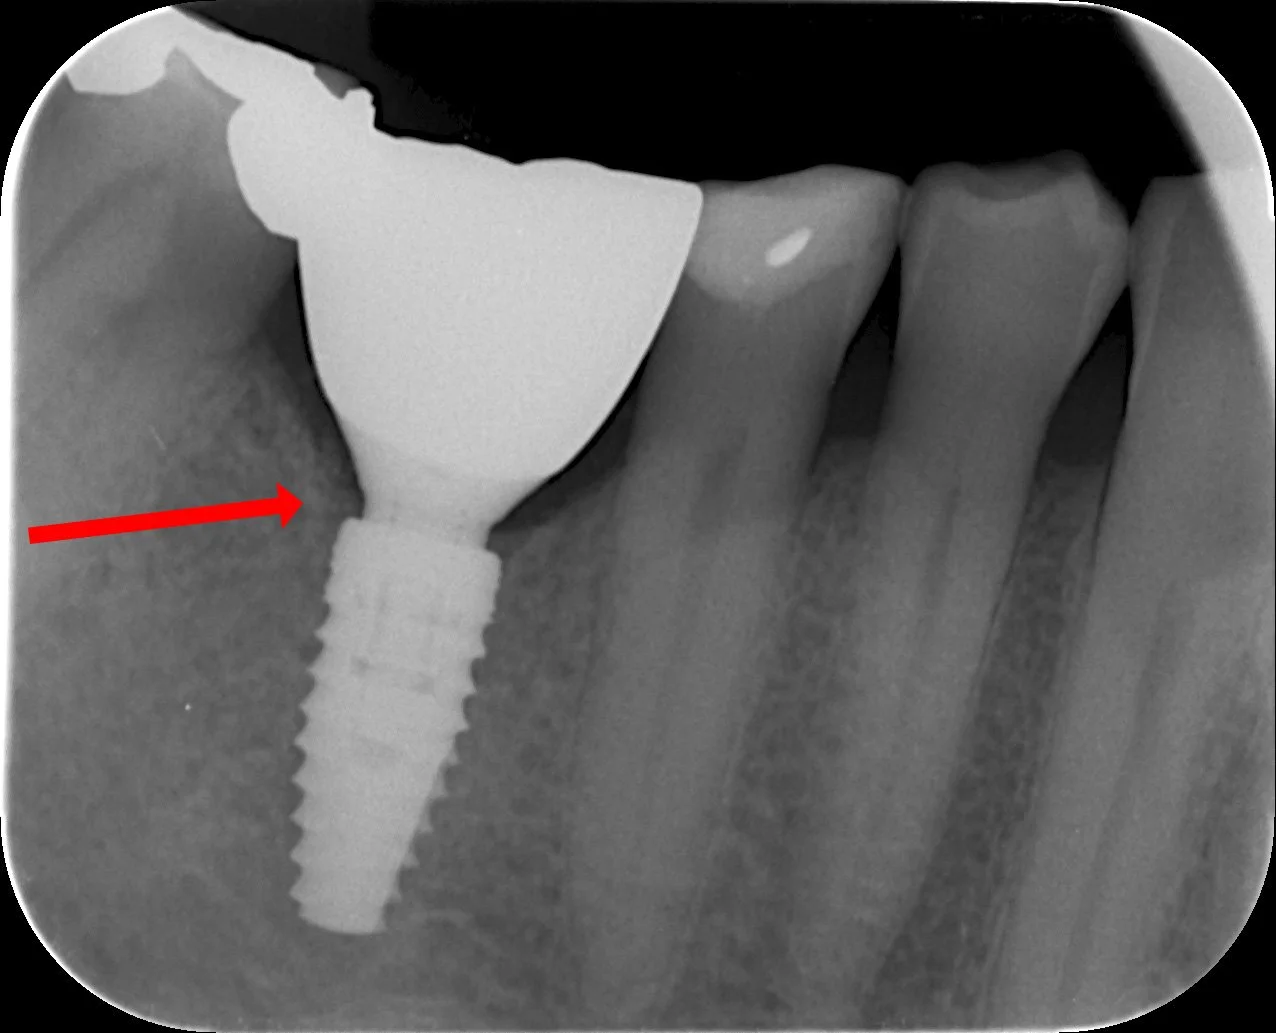

JATKEONGELMIA

Jatke painaa mesiaalisesti ja aiheuttaa kipua potilaalle yli 6kk ajan

Kruunu irrotettu, jatke hiottu ja kiillotettu. Vaiva poistunut.